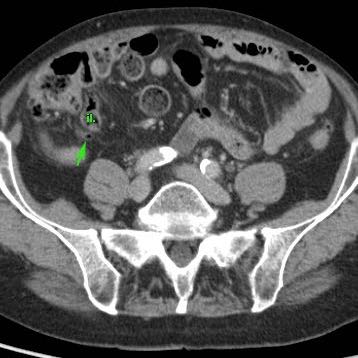

Ở bệnh nhân này, siêu âm cho thấy lượng lớn mô mỡ viêm (*) và hồi tràng dày thành, biểu hiện quá trình bao bọc thành công tình trạng thủng (sắp xảy ra) của ruột thừa (mũi tên).

Lưu ý sỏi phân vôi hóa (mũi tên trên CT) trong ruột thừa ở mức cao hơn.

Quá trình “bao bọc” này càng kéo dài, việc cắt ruột thừa sẽ càng khó khăn hơn.

Vấn đề nan giải này được thảo luận trong chương “khối ruột thừa”.